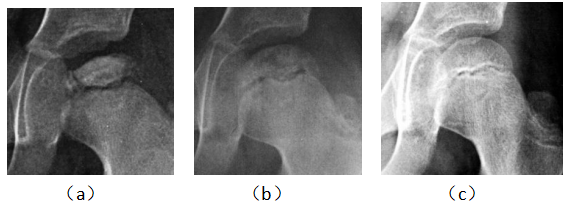

病例1男,29岁,患病2年,治疗15个月痊愈。治疗前,股骨头顶部塌陷、变平,顶部可见大块坏死骨,密度增高(a)。经过9个月的治疗,死骨与正常骨融合,密度减低,表面不清楚(b)。治疗后,股骨头略平,骨密度均匀,骨小梁清晰(c)

Case 1 male, 29 years old, 2 years sick, 15 months after eating. Before eating, the top of the femoral head collapsed, flattened, the top of the large dead bone, increased density, uneven thickness (a). After 9 months of treatment, the dead bone fused with the normal bone, the density decreased and the surface was unclear (b). After eating, the femoral head is slightly flat, the bone density is even, and the bone trabecula is clear (c).